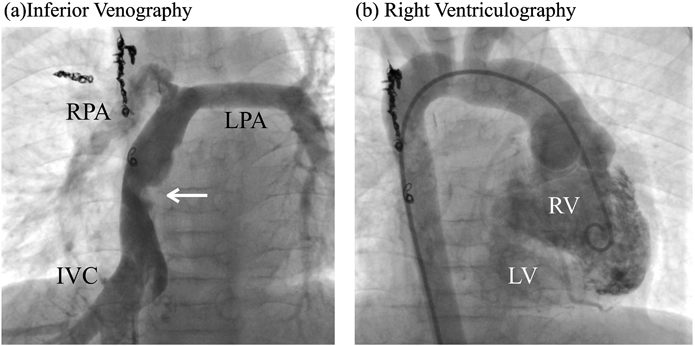

Fig. 3 Cardiac catheterization findings

(a) Inferior venography showing 50% stenosis in the extracardiac conduit (white arrow). (b) Right ventriculography showing no increase in right ventricle end-diastolic volume, a preserved right ventricular ejection fraction, and a small rudimentary left ventricle. IVC, inferior vena cava; RPA, right pulmonary artery; LPA, left pulmonary artery; RV, right ventricle; LV, left ventricle.

難治性PLEの原因評価と導管屈曲部の精査のため,心臓カテーテル検査が行われた.下大静脈造影では導管屈曲部の狭窄度は導管径の50%であった.肺動脈圧は17/15(平均15)mmHg,下大静脈圧は15/14(平均15)mmHgとやや高値であったが,屈曲部前後での引き抜き圧較差は0 mmHgであった.また,上下大静脈造影では明らかな側副血行路は認めず,導管屈曲部での造影剤の異常なpoolingも認めなかった.肺血管抵抗は1.57 unit·m2であった.右室拡張末期容積(right ventricular end-diastolic volume: RVEDV)は74.4 mL(Z score −0.41)と心拡大はなく,右室壁運動も良好で駆出率(ejection fraction: EF)は74%,心係数(cardiac index: CI)も2.59 L/min/m2と保たれていたが,拡張末期圧(right ventricular end-diastolic pressure RVEDP)14 mmHgと上昇を認めた.房室弁逆流はI度のみであった(Fig. 3).